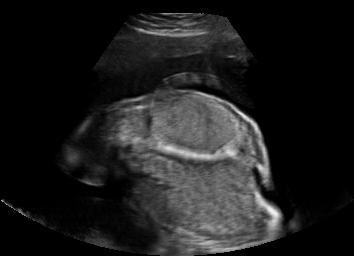

Real in-vivo images. 22 ultrasound sequences were collected using a GE Voluson E8 machine during standard fetal screening exams of 8 patients. Each sequence is several seconds long. We extracted all 4427 frames and resize them to , see Fig. 2 for some examples. The resulting image set was randomly split into training-validation-test sets by a 80-10-10% ratio.